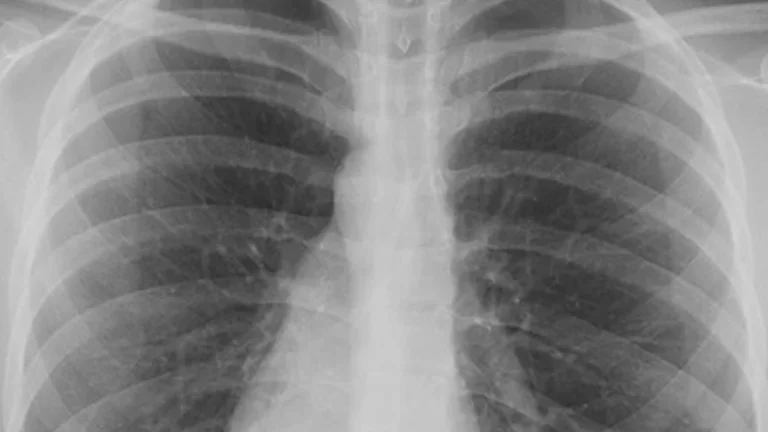

Certains patients gravement affectés par le SARS-Cov-2 présentent une forte et brutale dérégulation de leur système immunitaire. L’équipe de chercheurs en immunologie de l'Institut Biologie François Jacob (CEA) et de l’unité U976 HIPI (Hôpital Saint-Louis) à Paris s’intéresse au rôle particulier d’une molécule du système immunitaire, HLA-G, molécule dont elle est la spécialiste mondiale. Cette molécule pourrait avoir un rôle délétère dans une première phase puis bénéfique pour contrôler l’orage cytokinique. Le projet devrait permettre une meilleure compréhension de la physiopathologie du virus, apporter de nouvelles informations sur la réponse immunitaire incontrôlée observée lors d'une infection par le SARS-CoV-2 et proposer de nouvelles voies thérapeutiques pour une meilleure prise en charge des patients.

Pour atteindre leurs objectifs, les chercheurs vont étudier les paramètres immunitaires de plus de cent patients Covid-19 admis à l'hôpital, et ce pendant les premières semaines de la maladie en ciblant la molécule HLA-G et ses récepteurs, ainsi que les récepteurs au coronavirus SARS-CoV-2. Une partie des patients vient de la cohorte rétrospective COVIDeF2, l’autre partie est actuellement incluse dans le programme de recherche grâce au partenariat avec le Pr Olivier Brugière, pneumologue à l'hôpital Foch.